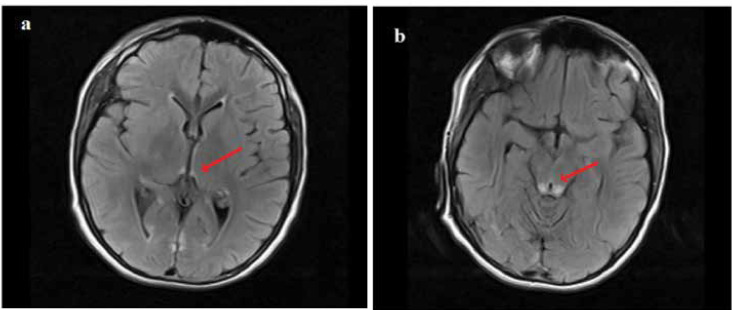

Dihydrolipoamide dehydrogenase (DLD) deficiency is a rare disease of genetic origin due to the malfunctioning of a shared subunit of three mitochondrial multi-enzyme complexes. Phenotypes of this disease are a set of clinical manifestations ranging from neonatal disorders to myopathy or recurrent episodes of liver failures, and vomiting for which no adequate or definitive treatment is currently available. This study described a case involving a 16-year-old boy who had experienced recurrent vomiting of unknown cause from age two. Normal value ranges for the basic metabolic panel were reported in previous years. The patient was admitted with Wernicke's encephalopathy after the last vomiting attack, also indicating metabolites of organic acids compatible with DLD deficiency. Whole exome sequencing identified a known pathogenic mutation in the DLD gene, leading to a diagnosis of DLD deficiency. Our patient was treated with a high dose of thiamine supplementation and continued treatment, has not experienced any vomiting attacks or related problems in the last two years and has adequately responded to the treatment prescribed. Normal urine organic acid levels in patients with recurrent vomiting cannot roll out DLD deficiency. However, although thiamine deficiency typically induces Wernicke's encephalopathy, it can also be implicated in pyruvate dehydrogenase complex (PDHc) deficiency, and high-dose thiamine therapy (with doses up to 30 mg/kg) is recommended for deficient patients.